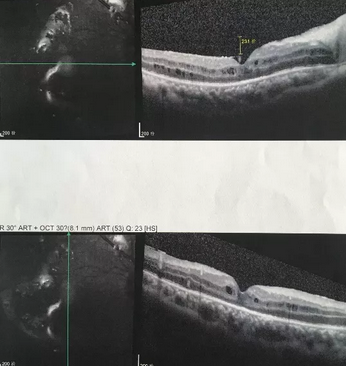

独眼,视网膜全脱离已成窄漏斗状、陈旧性葡萄膜炎、瞳孔后黏连无法散大,且并发白内障使得视网膜周边部细节情况无法看清,左眼已无光感,角膜白斑,瞳孔闭锁,还填充着硅油。右眼既往葡萄膜炎病因不清,一年中发病3、4 次都是用激素医治。左眼多年前是“天那水”溅入后又发生玻璃体出血手术后……令人担心的是这次我们克服重重困难救治全部脱离的视网膜 后,可能会面对长期慢性葡萄膜炎、长期药物医治的继发性高眼压,以及葡萄膜炎的再次复发等,稍有不慎就是不逆性致盲了。

葡萄膜炎等多种眼底病患者跪地感谢深圳6686 - 看球聊球追世界杯就来6686体育有限公司官方网站院长赵铁英教授3.png